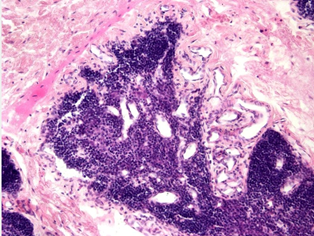

Which cells will be missing in a patient with congenital agenesis of the displayed organ?

image